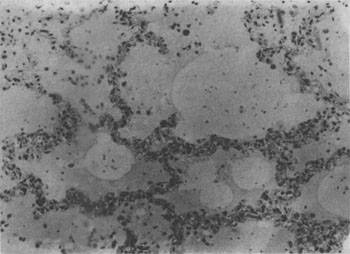

图3-16 肺水肿

肺泡腔内有水肿液及漏出的红细胞,肺泡壁毛细血管扩张充血

发生水肿的组织,体积增大,颜色苍白,镜下可见水肿液积于细胞和纤维结缔组织之间或腔隙内。由于水肿液含血浆蛋白,故HE染成粉红色。肺水肿时,肺泡腔内充满水肿液(图3-16)。切开肺时可有泡沫状液体自切面溢出。脑水肿时脑回变扁平,脑沟变浅。镜下,脑灰质和白质疏松,血管周围间隙加宽。严重时脑组织在高倍镜下呈网化状态。严重脑水肿时可形成脑疝。